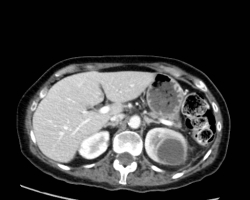

Les syndromes occlusifs, définis par l’arrêt complet du transit intestinal, regroupent quatre signes cliniques élémentaires : l’arrêt des matières et des gaz, les vomissements, la douleur et le météorisme abdominal, d’expression variable selon l’étiologie. […]